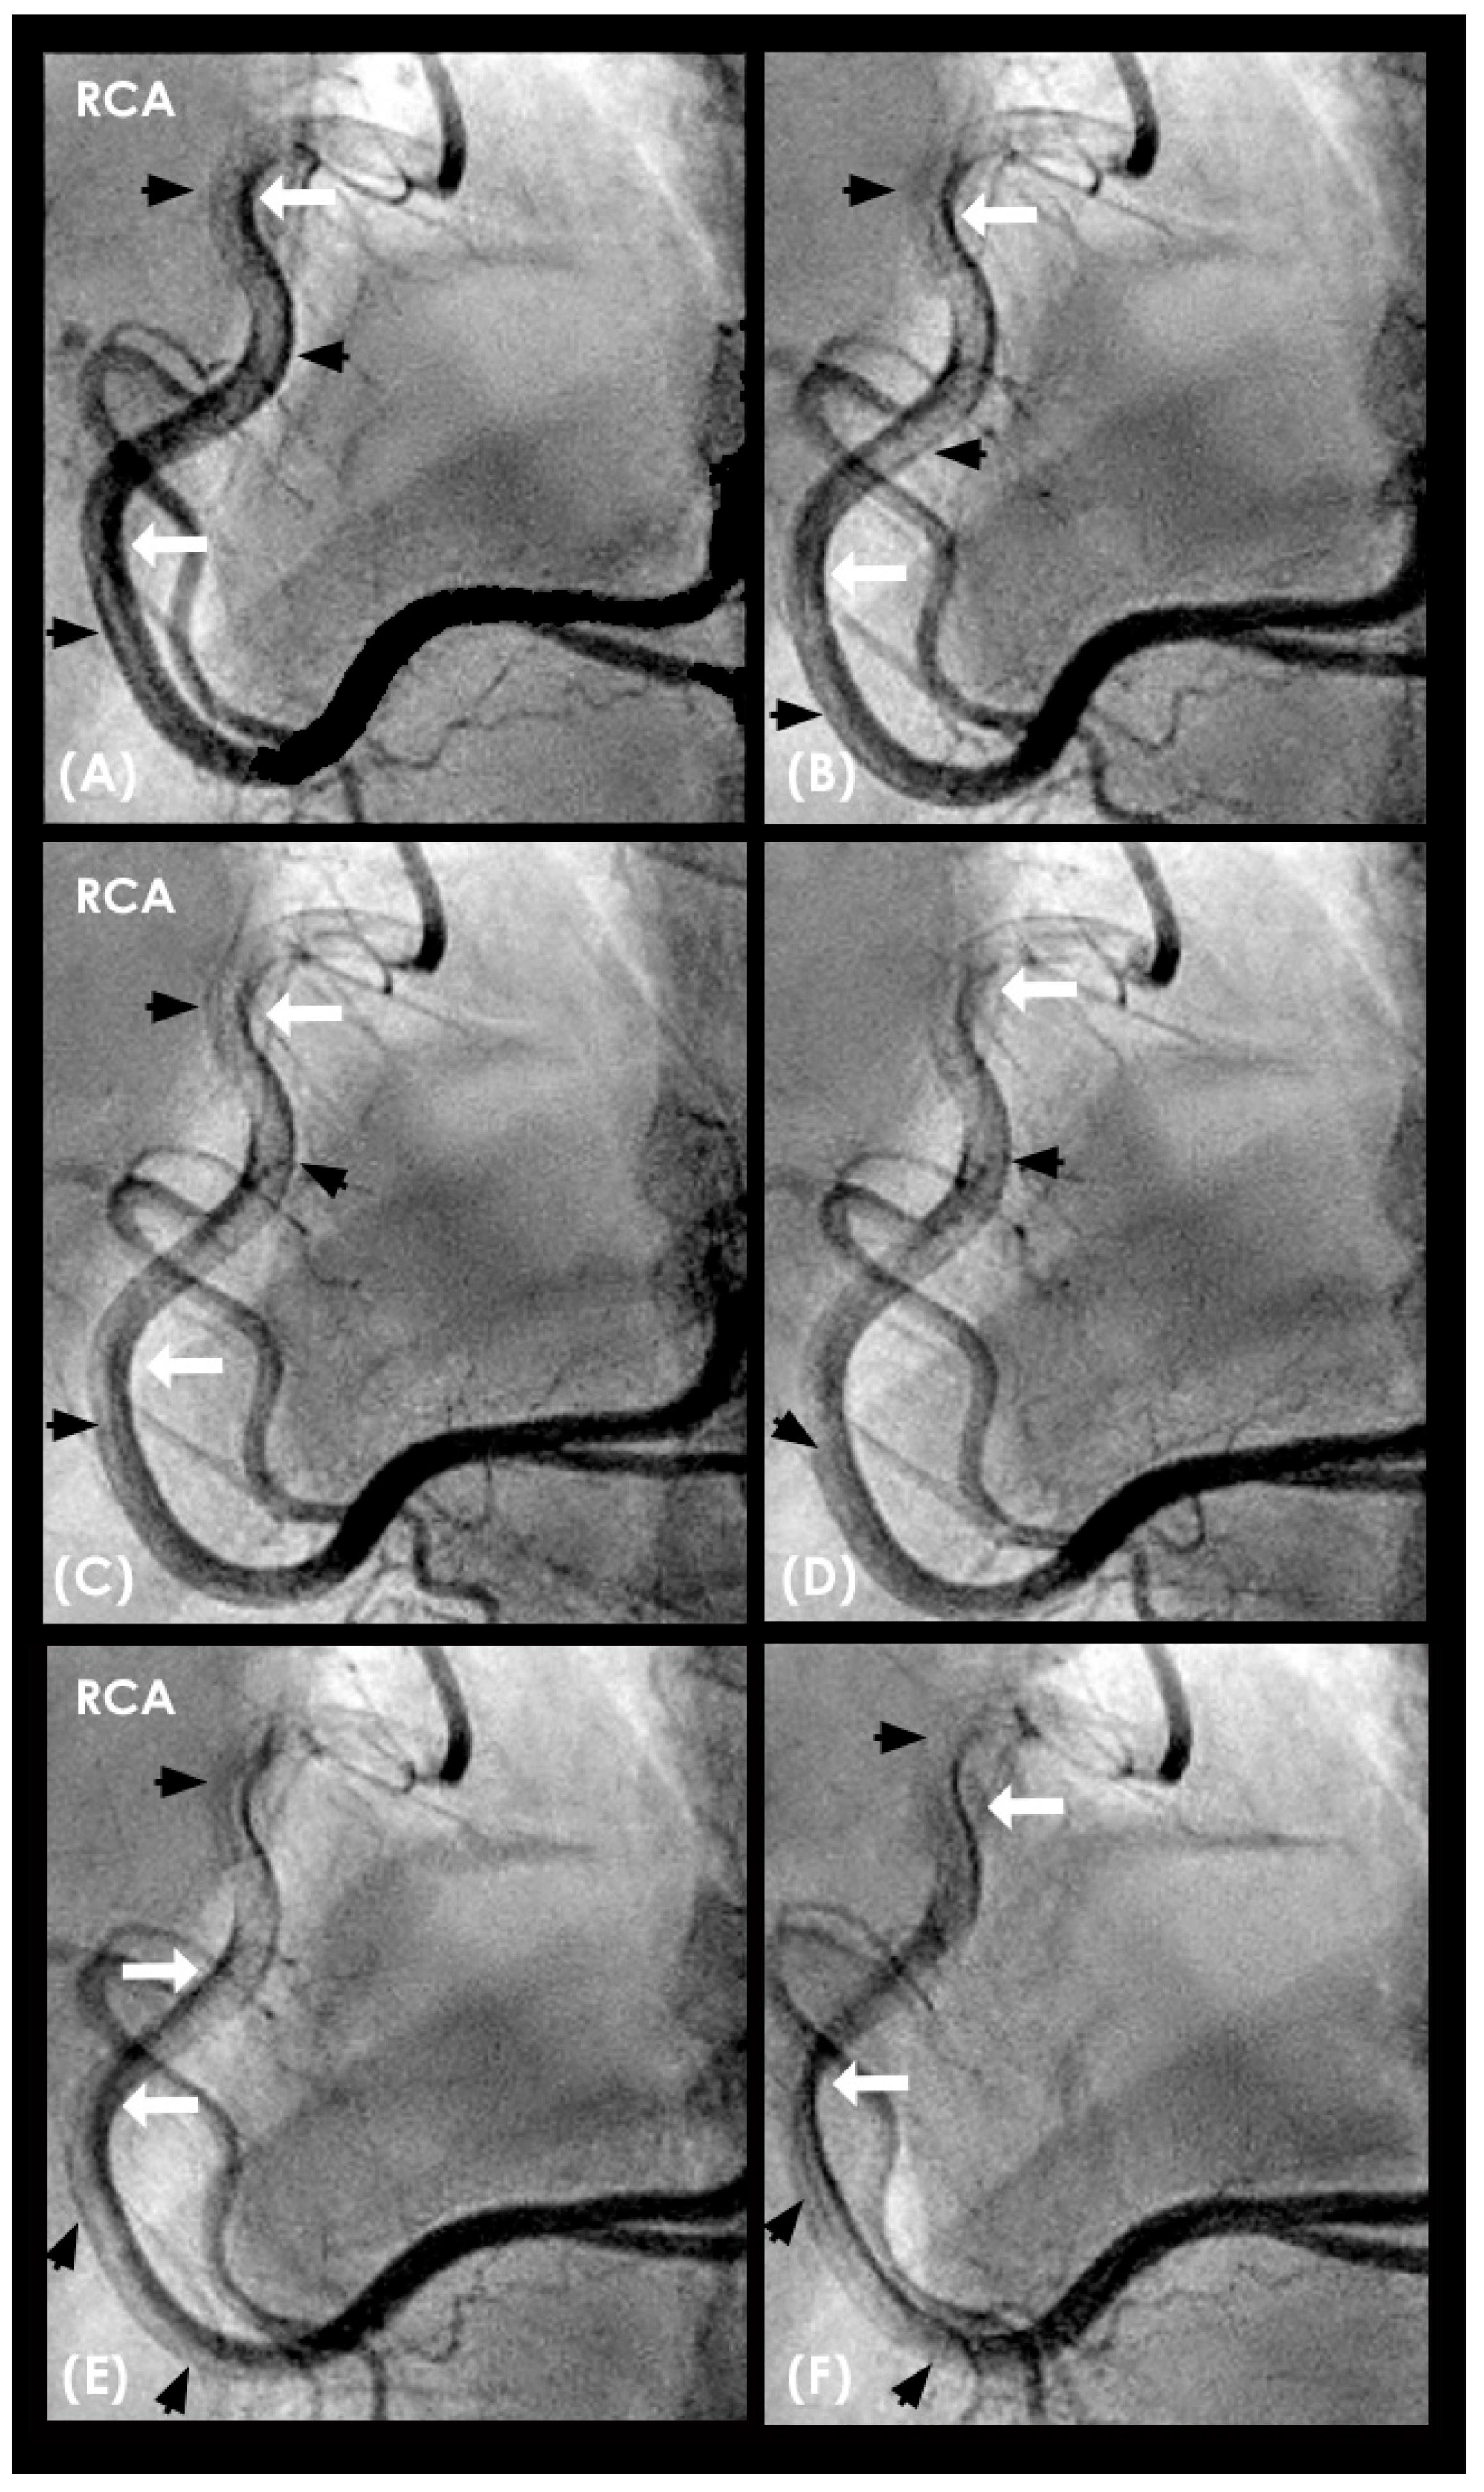

CLINICAL APPLICATIONS Ideal Systolic and Diastolic Blood Pressure. The first factor contributing to injury of the arterial intima is the nature of the blood flow. In young individuals with elastic coronary arterial walls and well-regulated blood pressure (systolic < 120 mmHg and diastolic < 80 mmHg), laminar flow progresses efficiently along the curvatures of the coronary arteries (Figure 20A–F). These conditions facilitate long-term cardiovascular stability and reduce the likelihood of development of coronary lesions [38]. This stability arises from the arterial wall’s capacity to absorb pressure surges, thereby attenuating pressure spikes that could otherwise damage the intima and initiate the atherosclerotic processes. Furthermore, maintaining low-density lipoprotein (LDL) cholesterol levels within recommended ranges is critical, as elevated total cholesterol—particularly in children with familial hypercholesterolemia—has been associated with early-onset coronary artery lesions [39].

Figure 3. (AD) Laminar flow. These four coronary images are of consecutive sequence. (A) This is the angiogram of the right coronary artery (RCA), which is filled with contrast in black. (B) The blood (in white) is seen well organized with sharp border and a pointed tip, typical for laminar flow, moving in (yellow arrow). (C,D) The blood is seen following the apex of the curves (yellow arrow). This is the laminar flow following the curves in a helical fashion.